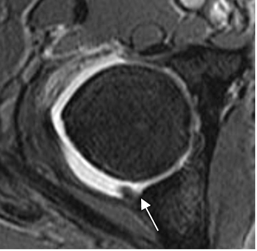

Fig 113. Ruptura del labrum.

A: Rx AP. Signos de pinzamiento tipo pincer.

B: ArtroRM coronal en STIR. Defecto del labrum superior, por ruptura. (Flecha gruesa).

Fig 114. Ruptura del labrum.

B: ArtroRM axial en STIR. Defecto del labrum posterior, por ruptura.